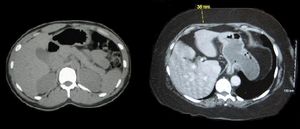

Two computed tomography images of a horizontal section of the mid-abdominal region; one from a normal-weight individual and the other from an obese person. In both, the bony structures and organs appear similar. The primary difference is that in the normal-weight person, there is little subcutaneous fat, and the obese person shows substantially subcutaneous fat.

정상 체중(왼쪽)과 비만인 사람(오른쪽)의 몸통 단면으로, CT 스캔으로 촬영되었다. 비만인 사람의 피하 지방은 이다.

피하 지방은 가장 널리 분포된 피하 조직층이다.[1] 이는 결합 조직에 의해 분리된 소엽에 함께 그룹화된 지방 세포로 구성된다. 지방 세포의 수는 신체 부위마다 다르며, 크기는 신체의 영양 상태에 따라 다르다. 이는 완충 작용을 하고 에너지 저장소 역할을 하며, 절연을 통해 약간의 체온 조절을 제공한다. 피하 지방은 피부 바로 아래에서 발견되며, 복강에서 발견되는 내장 지방과는 대조적이다. 체지방 캘리퍼를 사용하여 측정하여 총 체내 지방도를 대략적으로 추정할 수 있다.

2. 2. 피하 지방

피하 지방은 가장 널리 분포된 피하 조직층이다.[1] 이는 결합 조직에 의해 분리된 소엽에 함께 그룹화된 지방 세포로 구성된다. 지방 세포의 수는 신체 부위마다 다르며, 크기는 신체의 영양 상태에 따라 다르다. 피하 지방은 완충 작용을 하고 에너지 저장소 역할을 하며, 절연을 통해 약간의 체온 조절을 제공한다. 피부 바로 아래에서 발견되며, 복강에서 발견되는 내장 지방과는 대조적이다. 체지방 캘리퍼를 사용하여 측정하여 총 체내 지방도를 대략적으로 추정할 수 있다.